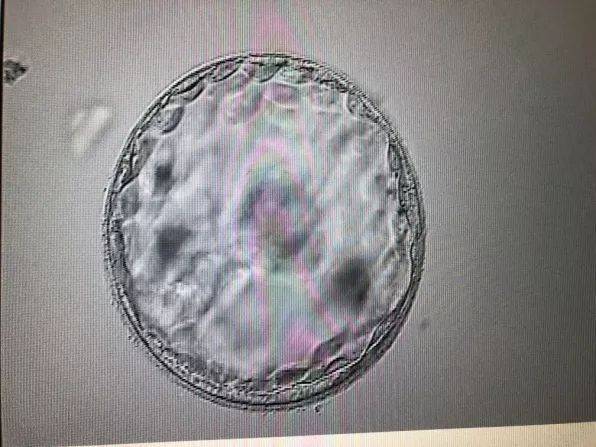

B超检查:观察胎儿发育情况,了解胎位、胎盘位置等。

四维彩超:更全面地观察胎儿发育情况,了解胎儿面部、四肢等。